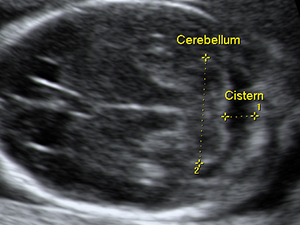

Fetal cerebellum at 17 weeks